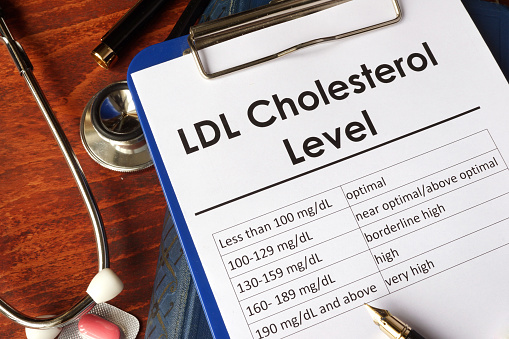

World heart day: Enlarged heart, diabetes and heart disease, fluid around the heart, massive heart attack